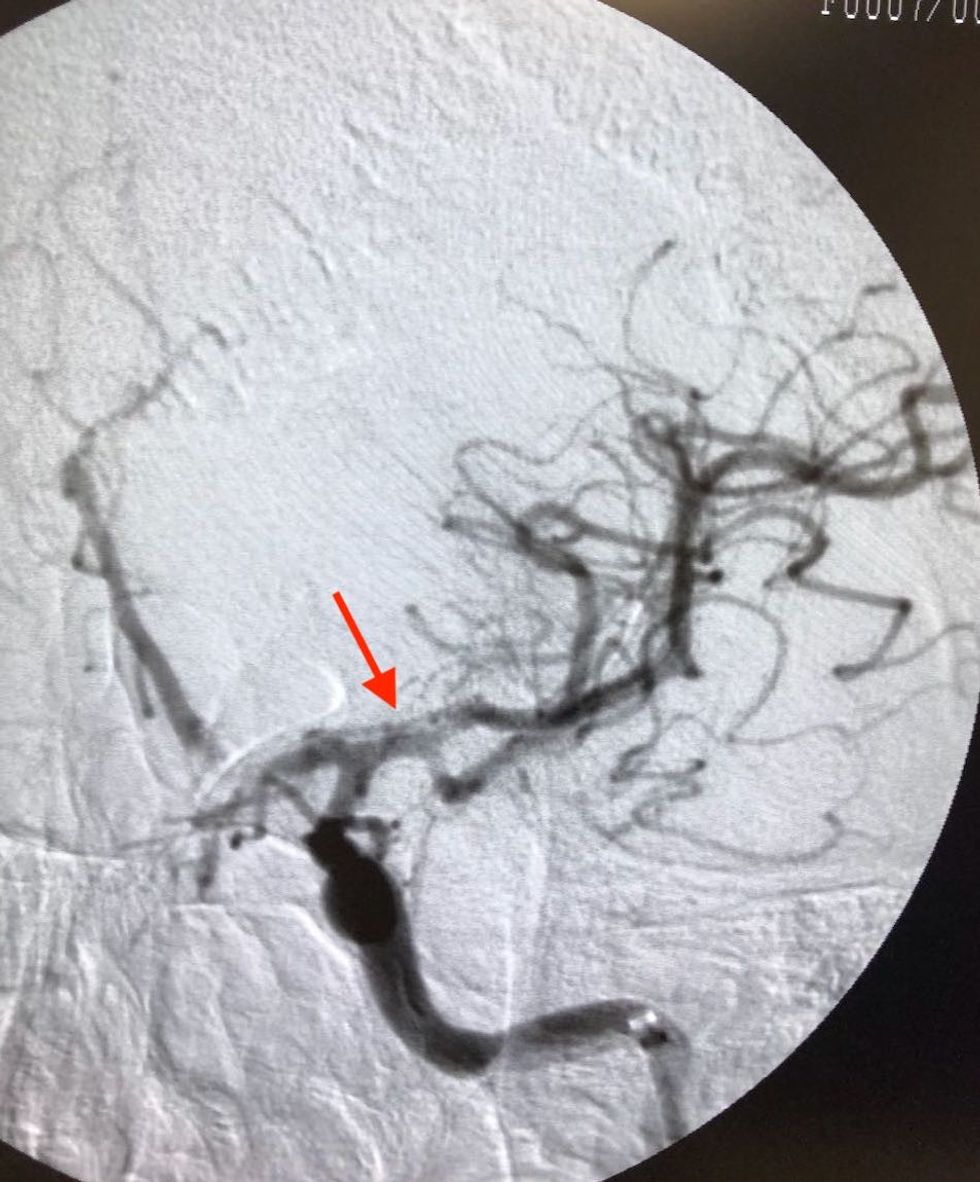

Realizohet trombektomia mekanike dhe rivendoset qarkullimi në pjesën më të madhe të ACM djathtas.

Imazhet me ADS konfirmojnë rihapjen e ACM djathtas

Pacientja rikthen në masë të madhe lëvizshmërinë e gjymtyrëve majtas e cila duhet stimuluar më tutje me terapi fizikale.